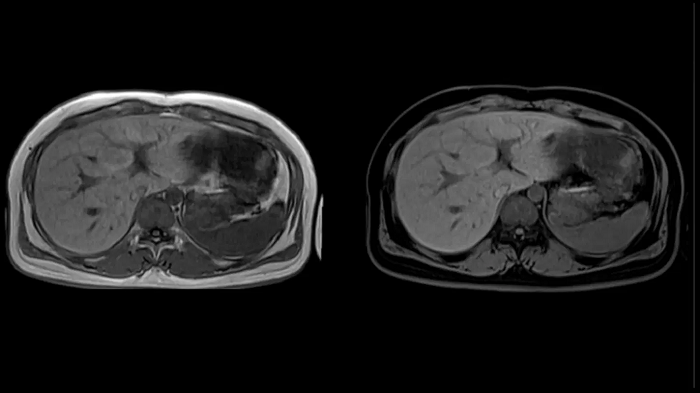

T1 VIBE Dixon with CAIPIRINHA

Get benefitted from Siemens Healthineers dedicated CAIPIRINHA acceleration to gain a complete abdominal volume within a single breath-hold. The Dixon technique offers outstanding fat water separation for a flawless representation of the abdominal anatomy.

MAC-ID: 7aaaa0165.

MAC-ID: 7aaaa0165. Image Credit: Siemens Healthineers

Body diffusion imaging

For all-inclusive abdominal MR capabilities, outstanding quality diffusion imaging.

T2 BLADE

T2 motion insensitive abdominal imaging with BLADE results in outstanding outcomes, regardless of the orientation or if fat saturation is needed.